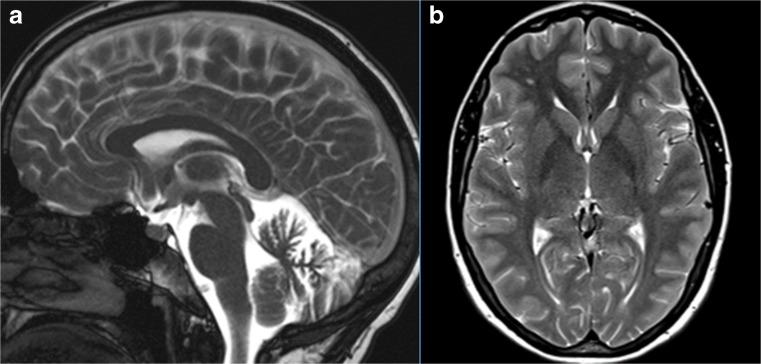

Structural Brain Imaging and [18F] FDG PET

The imaging data are summarized in Table 1 and are shown in Figs. 2, 3, 4, 5, 6, 7, and 8. Brain MRI revealed atrophy of the vermis and supratentorial white matter hyperintensities (WMH) in patients III:1 and III:2 and to a lesser degree in the index case (Figs. 2, 3, and 5). These WMH were particularly widespread in III:1 (Fig. 2). The index case was not affected by any other comorbidity usually associated with WMH, suggesting that these abnormalities may be an underlying feature of SCA19/22. WMH were not evident in the youngest patient (V:1). [18F] FDG PET revealed hypometabolism in the entire cerebellum, thalamus, prefrontal cortex (PFC), and parietal regions of the index case (IV:1) (Fig. 6). Her mother had reduced glucose metabolism not only in the PFC but also in the vermis as wells as in the motor and temporal cortex (Fig. 4). The youngest patient (V:1) had hypometabolism in the PFC, parietal, and inferior temporal regions but surprisingly not in the cerebellum (Fig. 8). In the latter structure, atrophy of the vermis was evident (Fig. 7).

Fig. 5.

Brain MRI of patient III:2. a Midsagittal T2-weighted image shows mild vermis atrophy. b Punctate white matter hyperintensities in the frontal lobe are evident in the coronal T2-weighted image